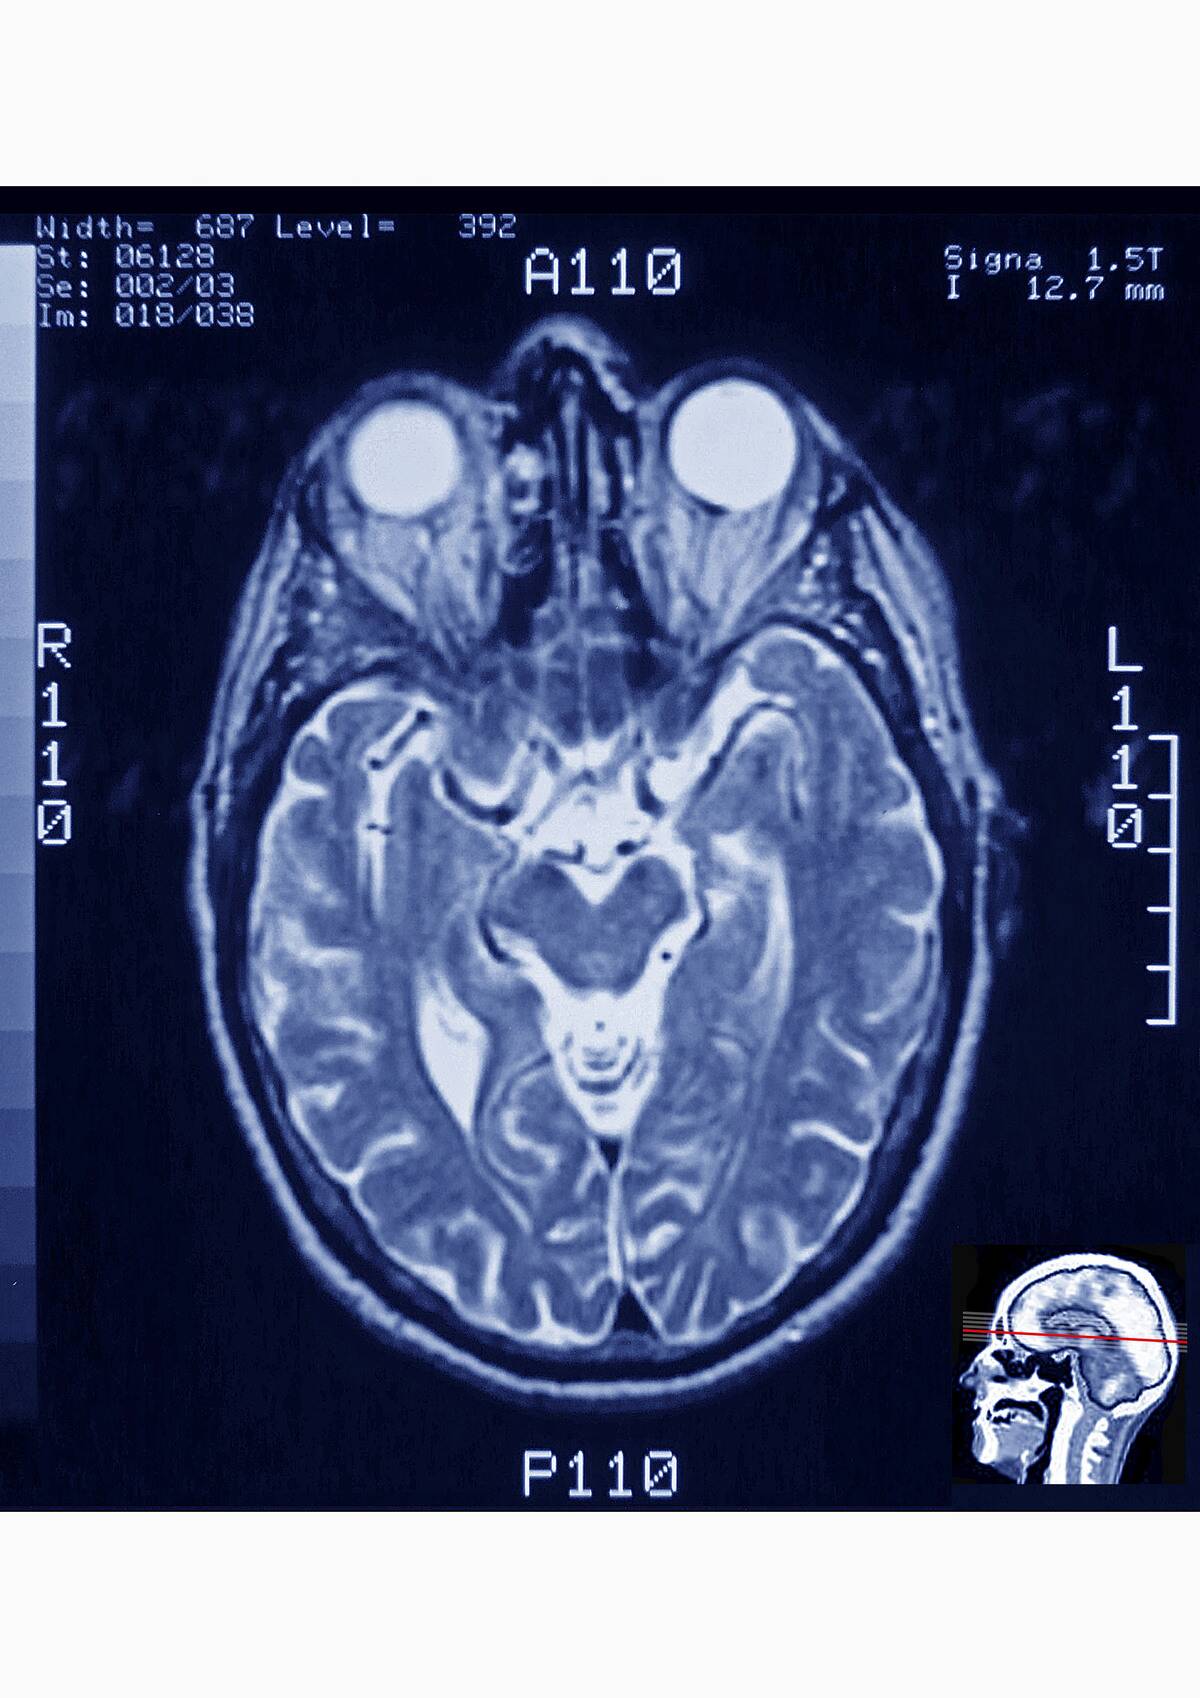

When we feel overwhelmed, our brain’s prefrontal cortex, responsible for decision-making and problem-solving, can become overloaded. This overload results from excessive neural activity, making it harder for the brain to function optimally.

The amygdala, a small almond-shaped cluster of nuclei in the brain, plays a central role in processing emotions. When you feel overwhelmed, the amygdala becomes highly active, signaling the brain that something requires urgent attention.